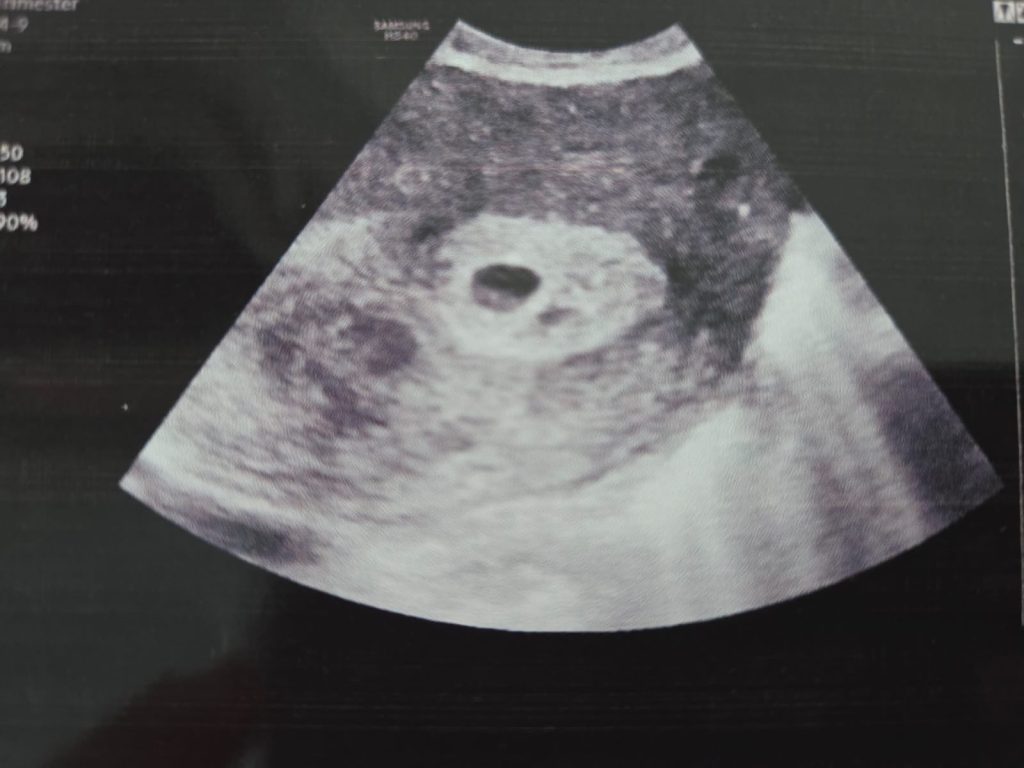

Gebelik kesesinin ultrason görüntüsü, rahim içindeki bir küre olarak tanımlanır. İlk olarak, gebeliğin doğrulanması için transvajinal ultrason yapılır. Bu, vajinal bir probun kullanılmasıyla gerçekleştirilen bir ultrason türüdür ve daha net görüntüler elde etmeye yardımcı olur. Gebelik kesesi, bu aşamada tipik olarak küçük bir yapı olarak görünür ve içinde embriyo henüz belirgin değildir.

Sonuç olarak, gebelik kesesi genellikle gebeliğin 4 ila 5 haftası arasında ultrason ile görülebilir. Ancak her kadında farklılık gösterebilir ve bazı durumlarda gebelik kesesi biraz daha geç ya da erken görülebilir. Bu nedenle, gebelik belirtileri yaşayan veya gebelik şüphesi olan kadınlar, doktorlarıyla iletişime geçmeli ve gerekli testleri yaptırmalıdır.